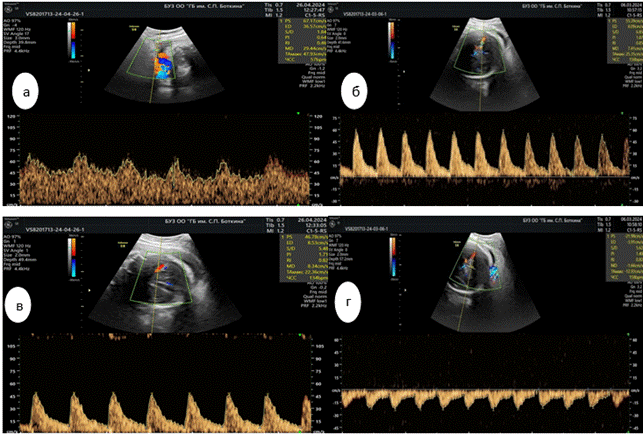

Величины мозгового кровотока плода в основной группе зависели от степени тяжести преэклампсии на фоне ХАГ. Значения максимальных скоростей в передней мозговой артерии (ПМАСДО) плода и периферического кровообращения в задней мозговой артерии (ЗМАPI) плода были статистически значимы, при исследовании установлены статистически значимые различия (p < 0,001). Так, величина соотношения показателей максимальных скоростей церебрального кровотока плода ПМА СДО плода основной группы на фоне тяжелой ПЭ в 3.28 раза превышала уровень ПМА СДО плода в контрольной группе, в 2.19 раза выше в группе сравнения (рис. 1).

Рис. 1. Доплерометрические показатели церебрального кровотока в ПМА: а) основная группа, тяжелая ПЭ; б) основная группа, умеренная ПЭ; в) группа сравнения; г) контрольная группа

Источник: составлено авторами на основе полученных данных в ходе исследования.